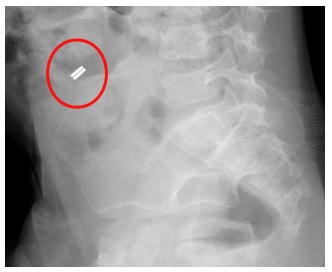

Dopo qualche giorno, sebbene il bambino scaricasse feci semiliquide 2-3 volte die, non aveva ancora eliminato il corpo estraneo che all'ennesima Rx risultava localizzato nella medesima posizione della lastra precedente; questa volta abbiamo eseguito una Rx anche in proiezione latero-laterale, la quale mostrava un oggetto formato da 2 dischi metallici contigui divisi da uno stretto binario (Figura 2).

Figura 2. Rx in proiezione latero-laterale: mostra i due magneti.

Dopo aver continuato la terapia procinetica ancora per 48 ore senza alcun risultato, abbiamo deciso di sottoporre il bambino a laparoscopia esplorativa che ha evidenziato una fistola ileale transmesocolica causata dall'avvicinamento di due anse ileali in cui in ciascuna di esse era contenuta una calamita (Figure 3 e 4).

L�ingestione di magneti � ampiamente descritta in letteratura e rappresenta un grave rischio per la salute del bambino, portando potenzialmente a gravi complicanze come la perforazione. I �take home messages� di questo caso sono essenzialmente due: il primo � l�importanza di ricordare ai genitori di vegliare i figli quando giocano con giocattoli con componenti magnetiche; in secondo luogo, in caso di anamnesi muta, � utile fin da subito eseguire un Rx anche in proiezione latero-laterale. Avremmo infatti cos� compreso che, per morfologia, non si trattava di una disk battery, ma di due magneti adesi tra loro: spesso infatti non tutto � quello che sembra.